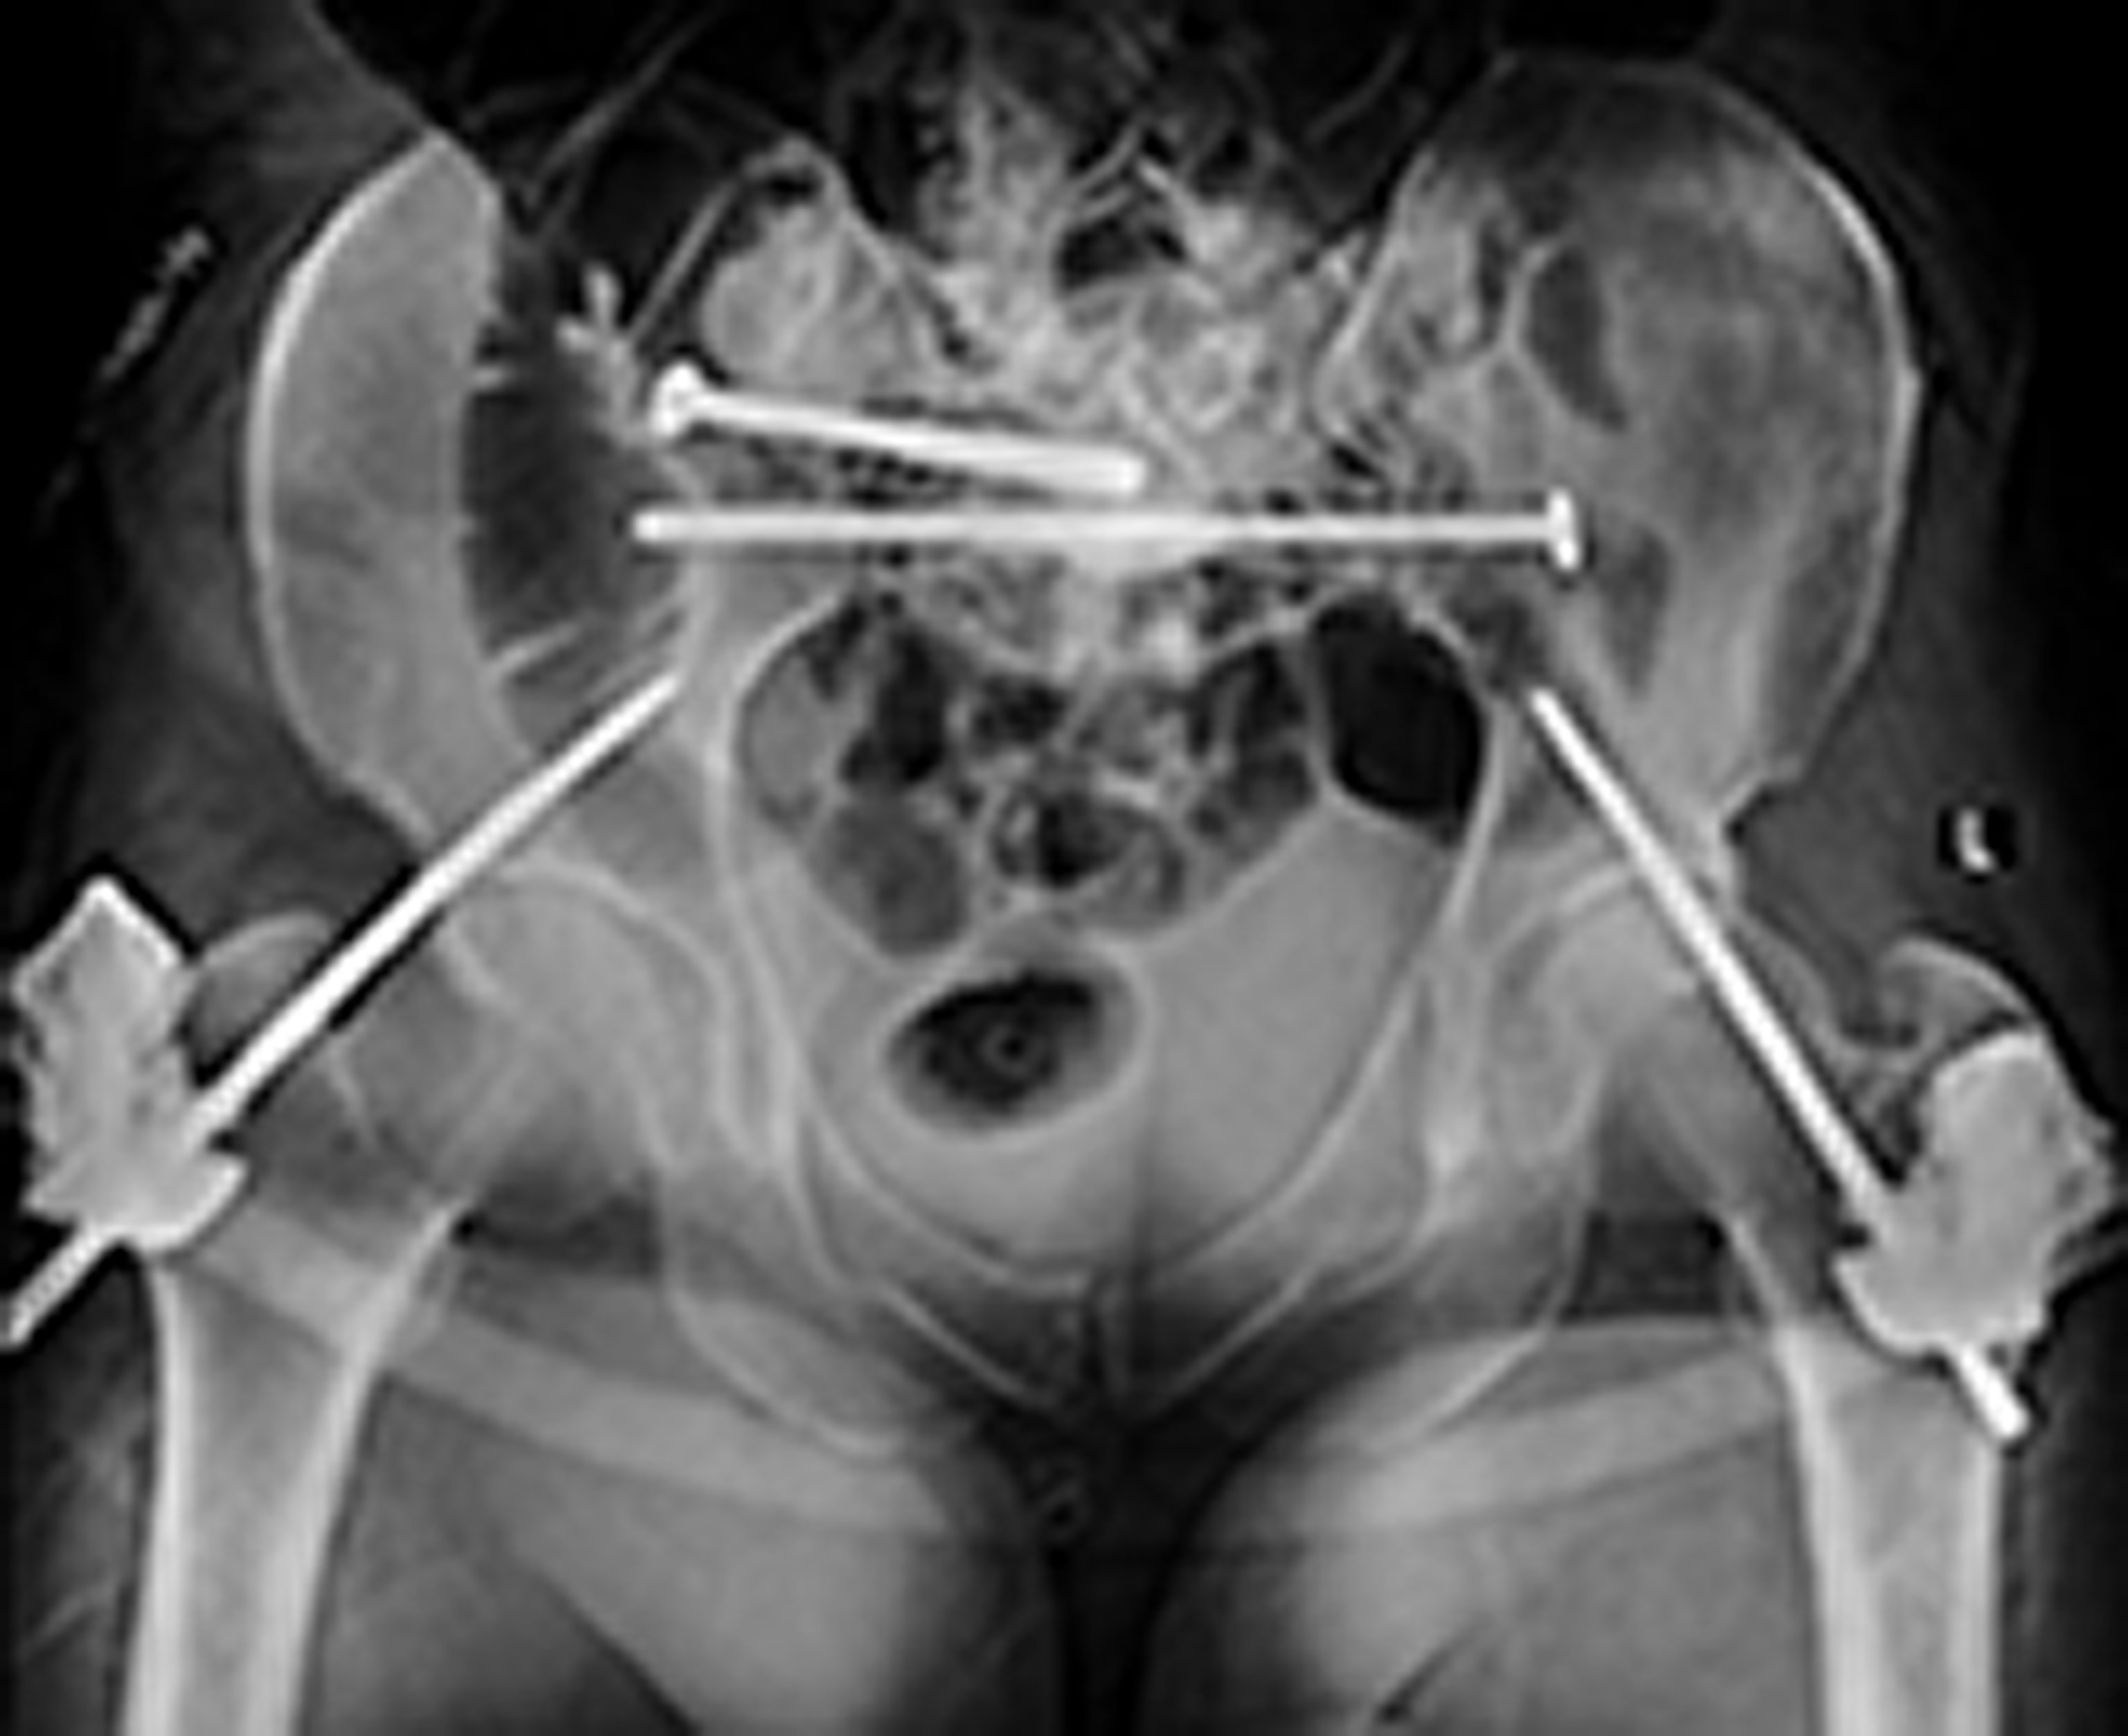

Our perception of pain isn’t limited to merely sensing it. The feelings of unpleasantness, fear, and anxiety that accompany the sensation are an integral part of experiencing pain. In a trial at the Cleveland Clinic, researchers led by neurosurgeon Andre Machado used deep brain stimulation (DBS) to target this emotional component of pain in 10 patients who had chronic neuropathic pain after suffering a stroke. The researchers implanted tiny electrodes in a part of the brain involved in processing emotions. Wired to an electronic device inserted in the chest, the electrodes delivered mild shocks to the implantation site at a rate of nearly 200 a second.